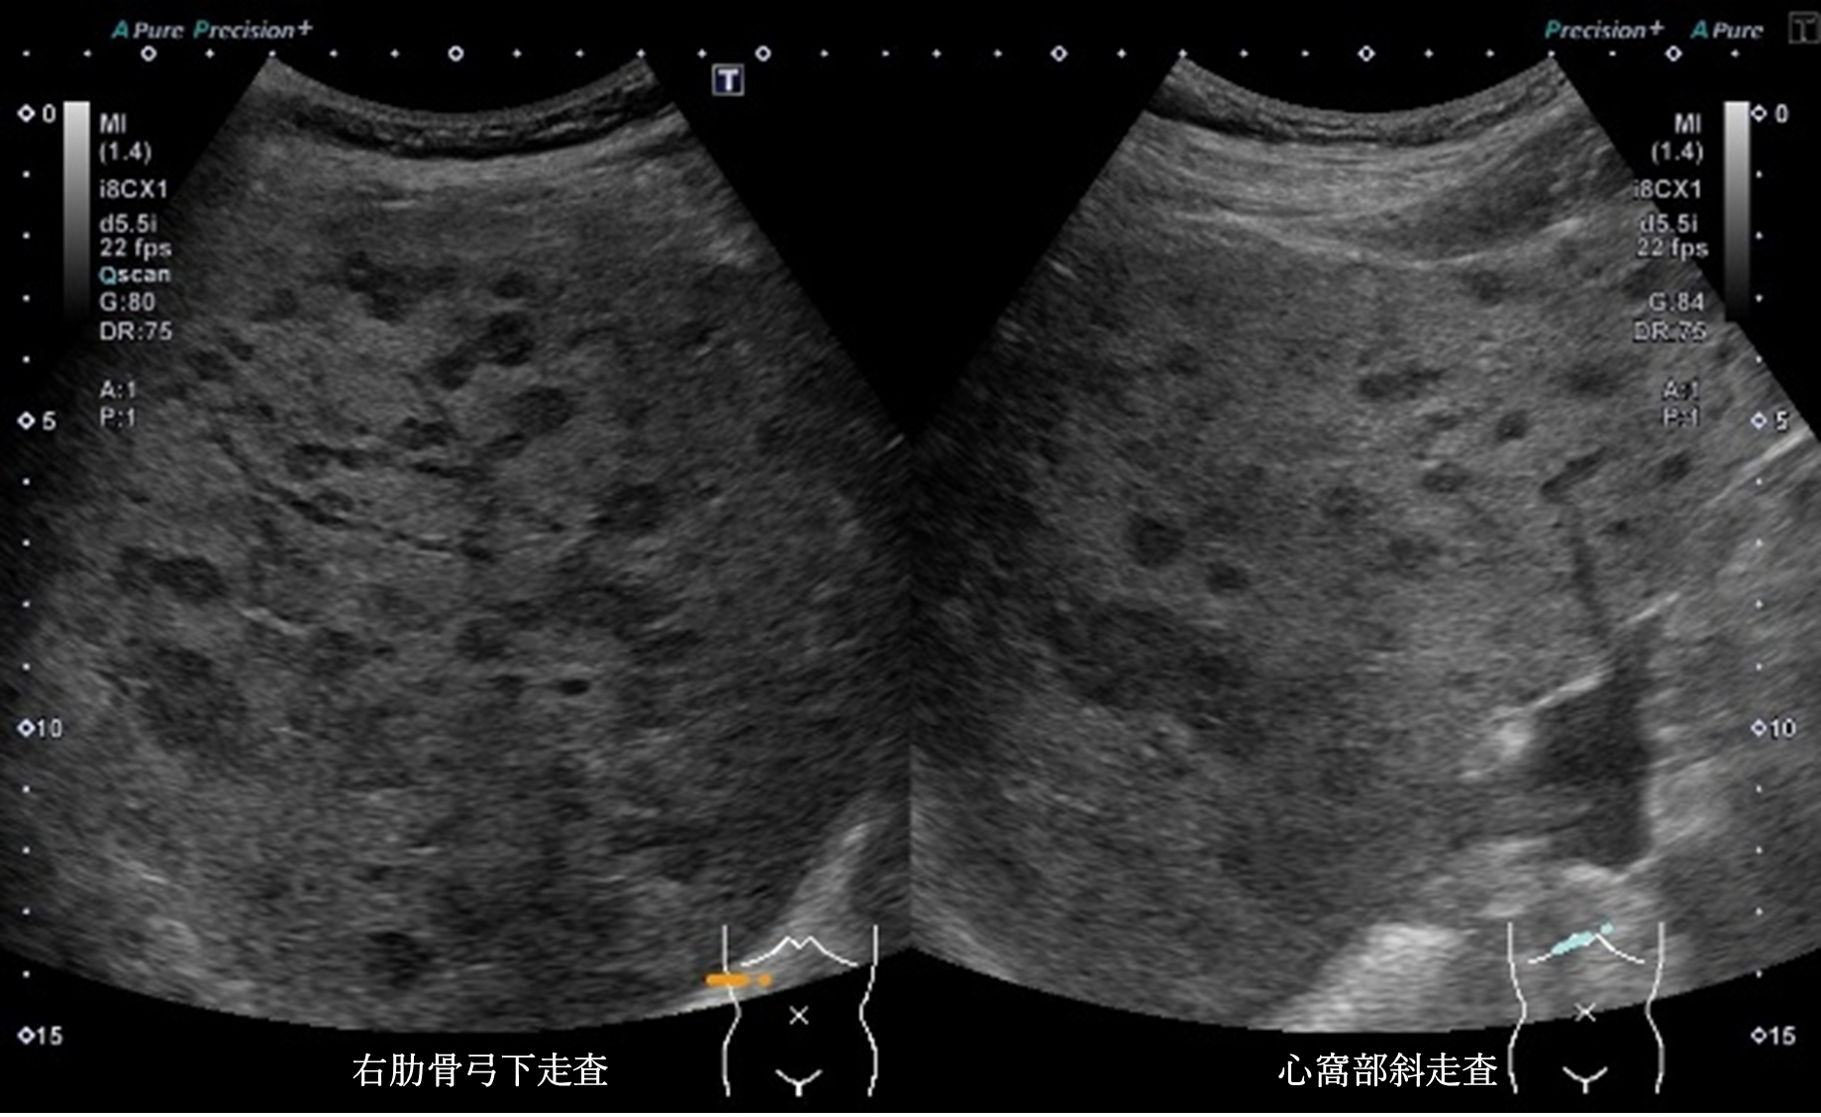

超音波所見より正しいのはどれか

① 肝全体に内部無エコーな腫瘤性病変を多数認める

② 肝全体に腫瘤性病変が多数みられ、辺縁低エコー帯を認める

③ 肝実質は粗雑不均質に観察され、明らかな腫瘤性病変は指摘できない

④ 肝全体に腫瘤性病変が多数みられ、腫瘤内部はモザイクパターンを呈する

⑤ 肝全体に腫瘤性病変が多数みられ、腫瘤辺縁にリング状高エコー像を認める

静止画および動画から超音波所見と考えられる疾患の組み合わせで正しいものはどれか

① bright loop ― 肝細胞癌

② 後方エコー増強 ― 肝嚢胞

③ nodule in nodule ― 肝細胞癌

④ bull’s eye pattern ― 転移性肝腫瘍

⑤ marginal strong echo ― 肝血管腫